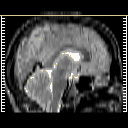

glioma overlay -- Slice #28

[Home][Help][Clinical] Slice 28

Click on sagittal image to select slice. Click on thin tickmark to change timepoint, or thick tickmark for overlay.